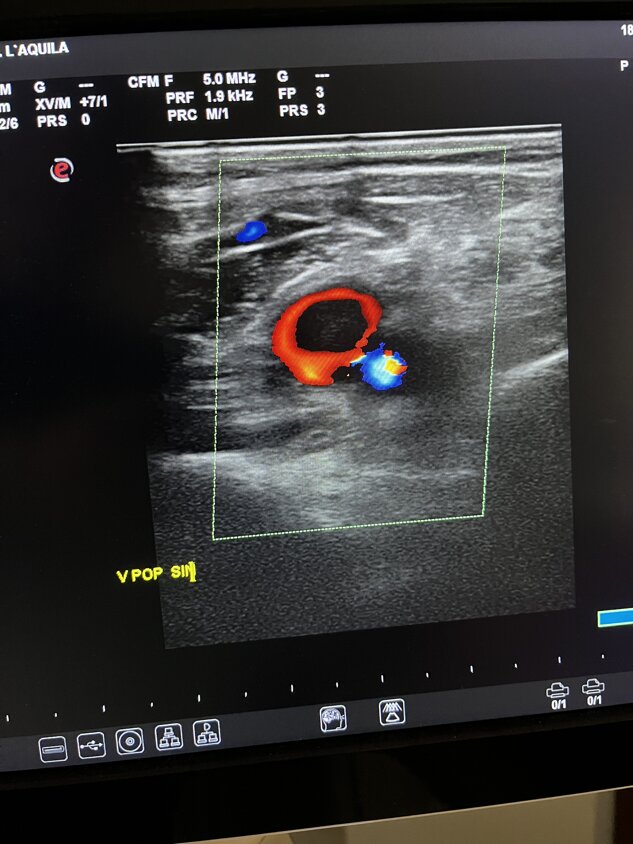

Ecocolordoppler

Tromboembolia polmonare

massiva in paziente con

trombo nella vena poplitea